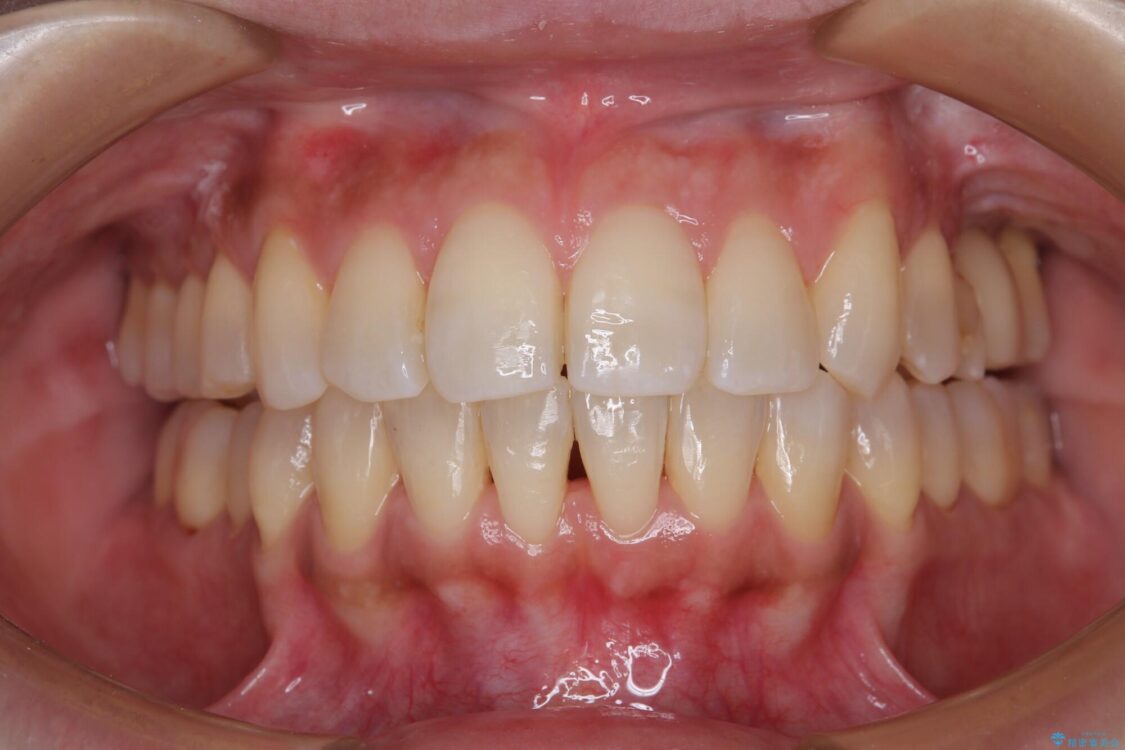

治療前

• インビザラインによる矯正治療と奥歯のインプラント治療 治療前画像

全体的なデコボコと、以前抜歯した歯のスペースを閉じた部分が気になるとのことで来院された患者様です。

左上第一大臼歯を抜歯した際に、スペースを閉じたそうですが、歯が傾斜してものが挟まって不快とのことでした。